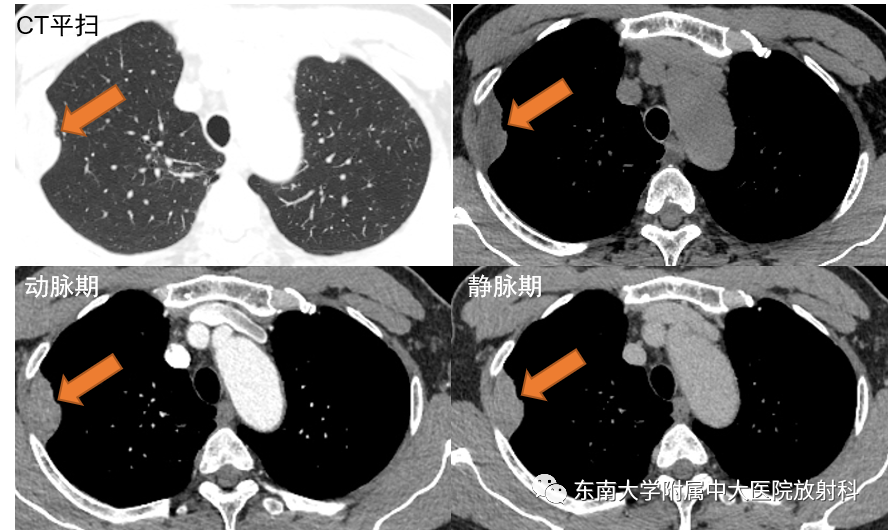

病例1

男,65岁,发现左侧腹股沟区可复性包块一月余